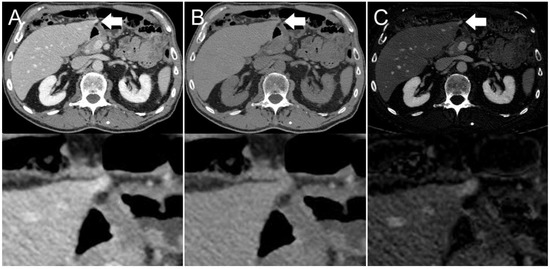

Figure 4. Axial contrast-enhanced CT scan of an 86-year-old man. Hyperdensity (indicated by arrows) on the left liver lobe in the (A) conventional 120 kVp image, which might be interpreted as a peristalsis-related streak artifact originating from the stomach. The (B) virtual non-contrast (VNC) image reconstruction and (C) iodine image reconstruction reveal that it is not a streak artifact, but a hyperenhancing liver lesion.

The presence of visible intestinal peristalsis-related streak artifacts on the liver was significantly lower (p < 0.001) in the iodine image reconstructions with 18/208 (9%) compared with the conventional 120 kVp images with 51/208 (25%) (see Figure 2, Figure 3 and Figure 4). The presence of visible peristalsis-related streak artifacts on the liver was not significantly lower in 40 keV monoenergetic image reconstructions with 48/208 (23%) (p = 0.15), 200 keV monoenergetic image reconstructions with 51/208 (25%) (p = 1.0), or VNC image reconstructions with 50/208 (24%) (p = 1.00) compared with conventional 120 kVp images.

Our findings support the notion that peristalsis-related streak artifacts have the characteristics of a highly attenuating tissue with spectral properties similar to water, as these artifacts affect the 40 keV and 200 keV monoenergetic image reconstructions to a similar degree and appear intensely on the VNC image but not the iodine image reconstructions [6]. Since iodine image reconstructions depict voxels with a relatively large decrease in HU between low kVp and high kVp images, streak artifacts are largely absent in the iodine images, revealing the underlying liver tissue enhancement [12]. Our study shows that iodine image reconstructions may improve diagnostic accuracy for cases with streak artifacts on the liver. Parts of the liver that are not clearly visible on conventional 120 kVp images because of peristalsis-related artifacts can be reliably evaluated by viewing iodine images of the same CT scan.